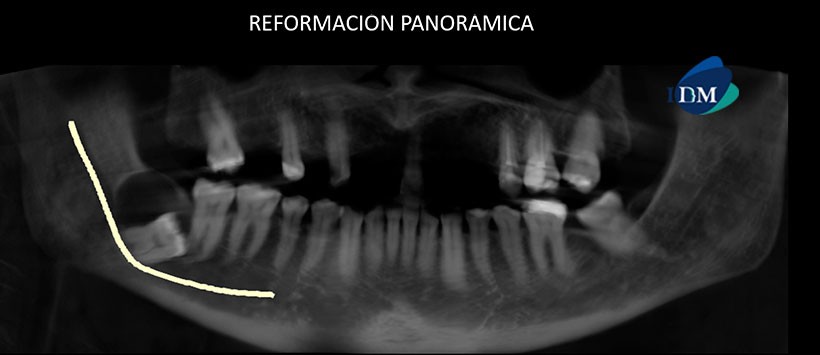

A la evaluación de la tomografía computarizada de haz cónico (CBCT), mediante reformación panorámica (Figura 1), cortes transaxiales (Figuras 2) y cortes tangenciales (Figura 3), se aprecia la impactación de la pieza 4.8 en posición horizontal, con presencia de una de una imagen hipodensa en relación a la corona de dicha pieza, de limites definidos, corticalizados, que ocasiona leve expansión y adelgazamiento de la tabla ósea lingual.

Así mismo, al evaluar la relación de la pieza impactada con el conducto dentario inferior se observa una estrecha relación entre ambas, encontrándose este último discurriendo por el medio de ambas raíces.

En las reconstrucciones 3D se observa claramente las imágenes antes descritas y su relación con estructuras adyacentes. (Figuras 4, 5 y 6)